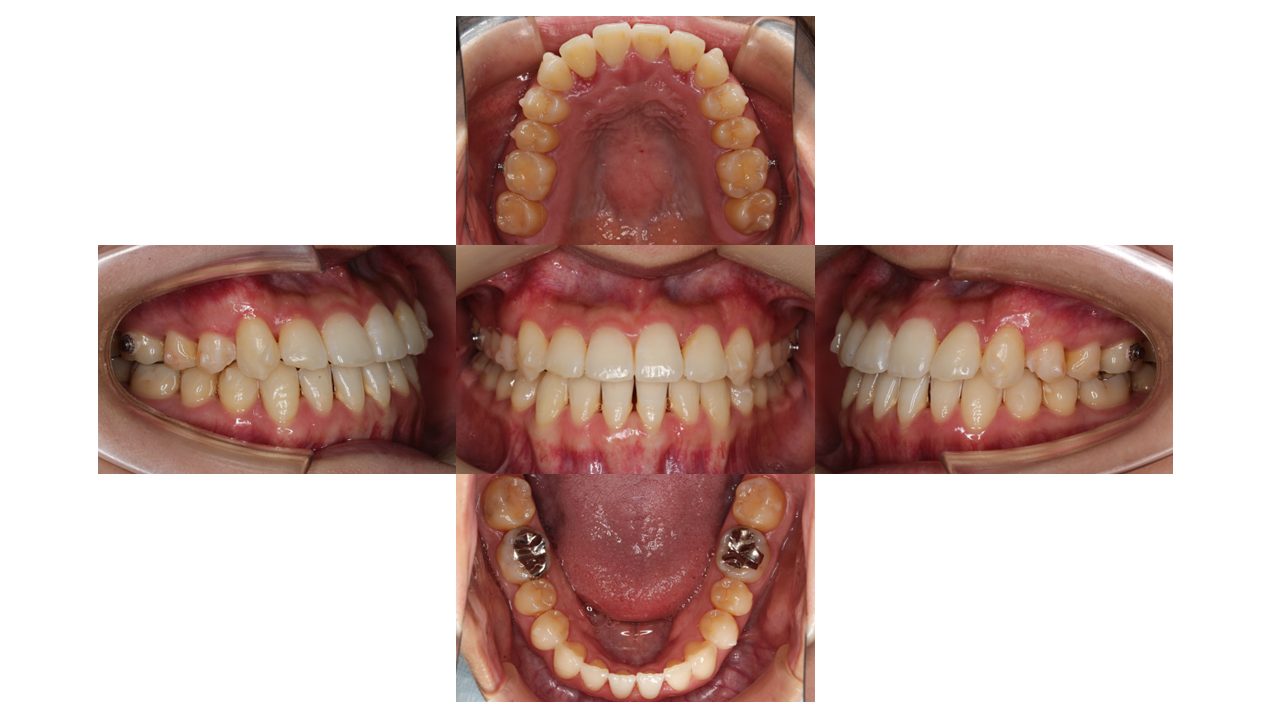

2年経過の口腔内の状態です。

残りのスペースと噛み合わせの調整をしていきます。